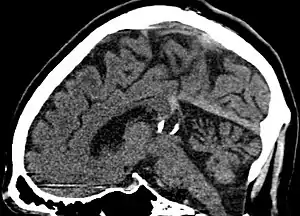

| Pineal gland cyst | |

| Calcified cyst of pineal gland in CT. Sagittal MPR. |